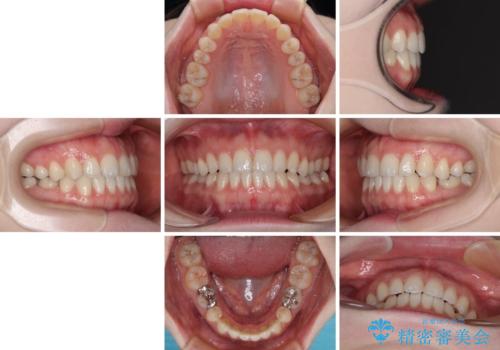

すきっ歯をインビザラインできれいな歯並びに改善

- 1年5ヶ月

隙間や叢生の程度はそれほど著しいものではなかったので、インビザラインでもワイヤー矯正でも対応可能でしたが、極力目立たない装置を希望されたため、インビザラインにて矯正治療を行うこととしました。